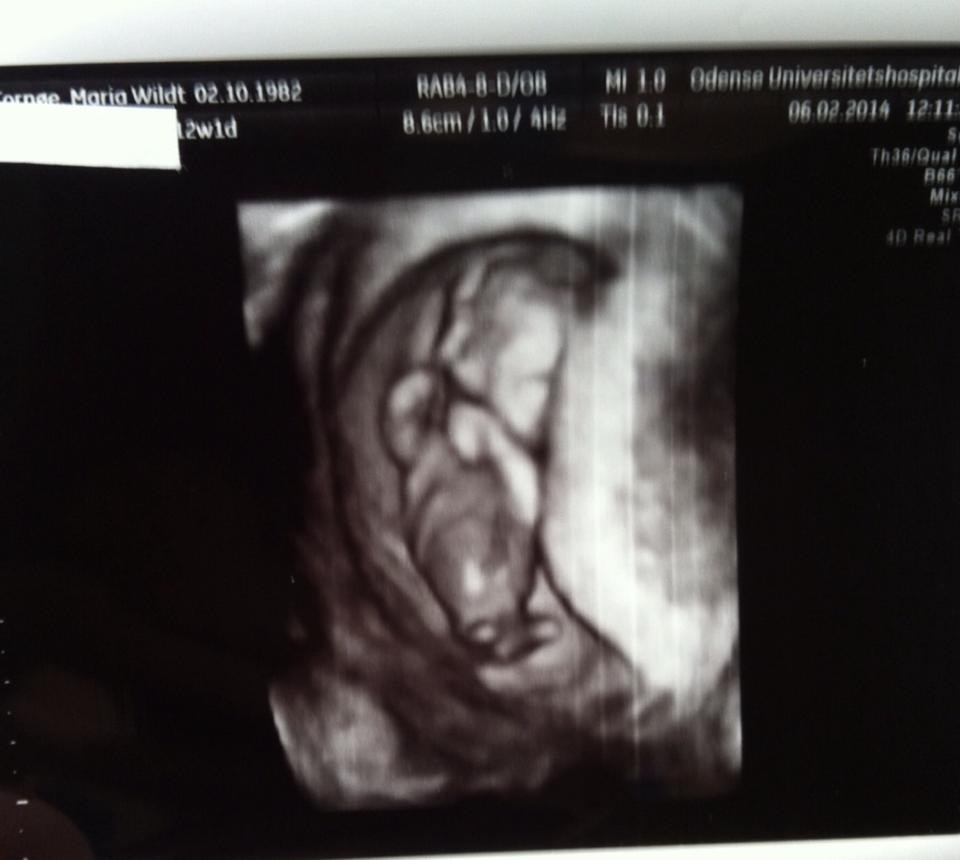

Alexander&Lærke skriver:

Tillykke med både graviditet og nakkefold scanningen.... Hvornår forventes bebs at ankomme?

Termin er sat til 15 August